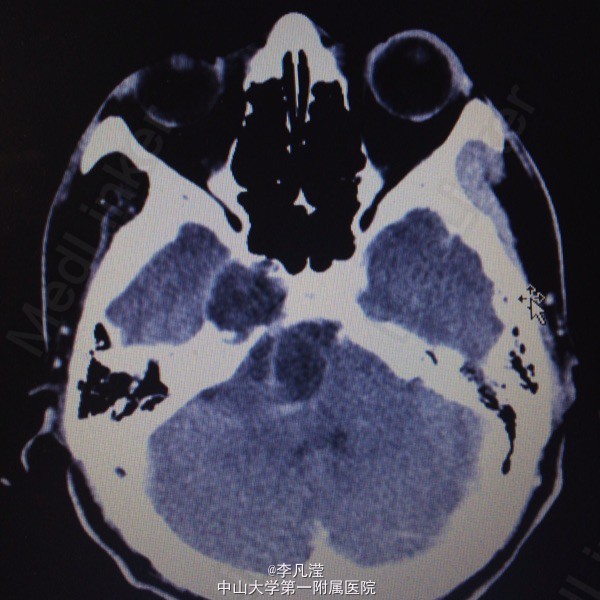

三叉神经鞘瘤一例

右侧中后颅窝底肿块,考虑三叉神经鞘瘤,右侧颞骨岩尖及海绵窦区骨质吸收,右侧麦氏孔扩大,侧脑室及第三脑室轻度积水。

右侧三叉神经鞘瘤